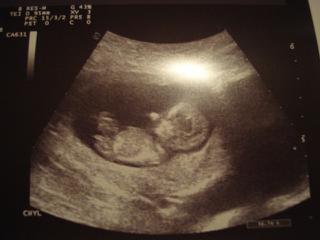

ahojte kolegynky, musim sa vam pochvalit, taka som cela stastna a v vytesena 😀 😀 😀 😀 😀 dnes sme boli na skriningovom sone, doktor bol uuuuzasny, perfektny pristup, vsetko mi poukazoval, miminecko sa ma super, meriame 4,7cm a vseeeetko mame v norme, az sa mi to nechce verit ze sme tak dobre dopadli 😅 😅 😅 skoro som sa rozplakala ked som male videla, tak strasne som sa bala ci je vsetko ok.. bol so mnou vnutri aj muz, doktor povedal ze malicke bude velke po ockovi ze nabuduce pozrieme 😀 dufam ze to nemyslel az tak vazne, muz mal porodnu vahu 4,5kg!! 😀 😀 😀 no a este povedal ze je to krasne zdrave babatko, pytala som si fotku, urobil mi za 5 eur, inak som nic neplatila, iba ze nabuduce na skrining vysetruju podrobne srdiecko a tam sa doplaca 10e.

a na konci mi dr vravi ze nepriberte vela, max pol kila za mesiac 😲 a bezal, mal cosi, to mi uz len tak z dveri krical..akoze nepripadam si tucna, mam 55kg a pribrala som 1kg, no neviem co tym xcel povedat 😀 😀 😀 😀 tesim sa so vsetkymi co tiez dobre dopadli a drzim na palceky! zajtra vam ukazem krpceka, pridam foto 😀 😀 cmuuuk

kukajte na nase mimciatko, zlate, ze? 😅 😅 😅 😅

@barborkach neviem, ale sa mi podľa tej fotky zdá, či to nie je chlapček, ale mám neskúsené oko, tak to môže byť ozaj len zdanie 😉